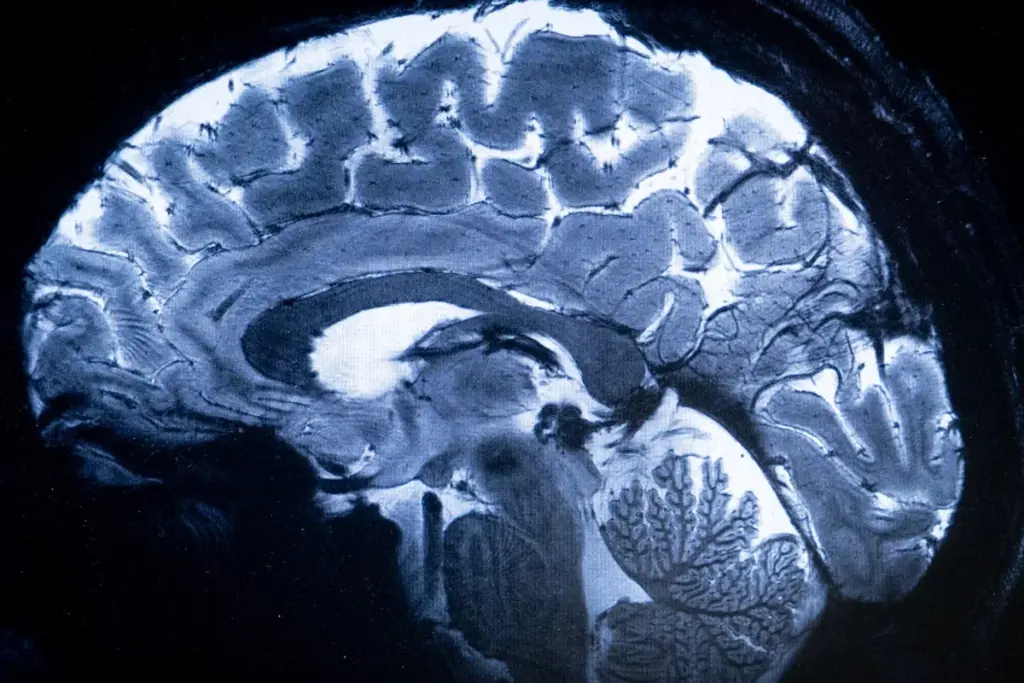

Brain MRI Experience: What to Expect

The brain MRI experience might seem scary, but it’s a simple test. Knowing what happens can make you feel better and get ready for it.

Does Your Whole Body Go In For a Brain MRI?

Many wonder if their whole body goes inside for a brain MRI. It depends on the MRI machine. Traditional ones have a tube that might scare those with claustrophobia. But, only your head goes in for a brain MRI.

If you’re worried about claustrophobia, there are other options. Open MRI systems or wide-bore machines offer more space. They can make you feel less anxious during the test.

Duration and Procedure for Head MRIs

A brain MRI usually takes 15 to 90 minutes. This depends on how detailed the scan is and if dye is used. You’ll lie on a table that moves into the machine. You’ll get earplugs or headphones to block out the noise.